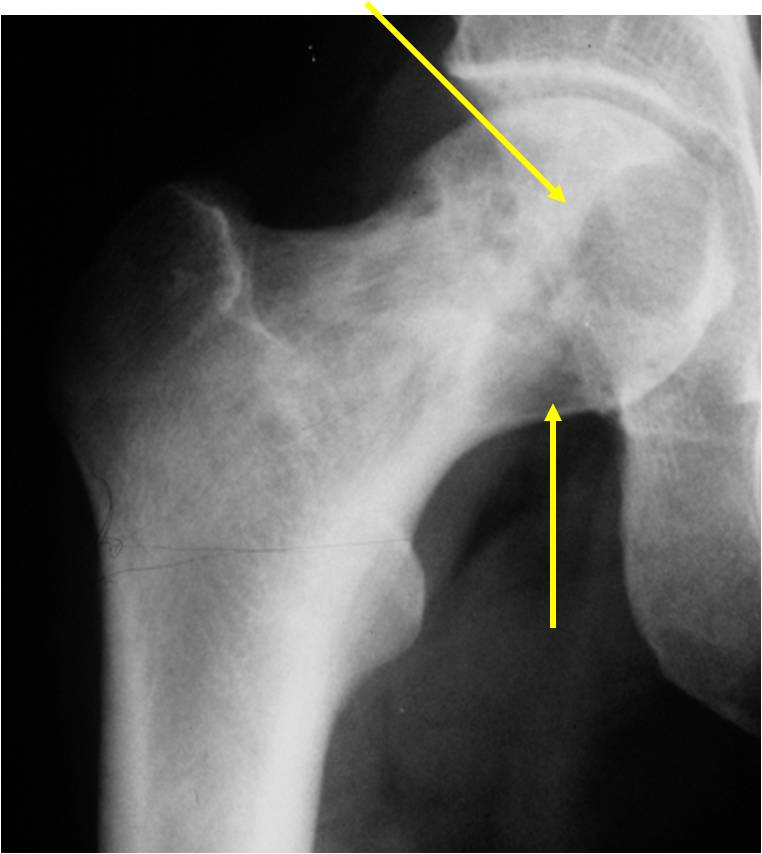

Sites:

- Epiphyses of long bones

- Most commonly proximal femur, proximal humerus, distal femur, proximal tibia

Radiographic Presentation

- Usually osteolytic, expansile lesion

- May be focally calcified

- Often a sharp interface between tumor and surrounding bone

- Sclerotic rim is uncommon

- Overlying cortex is usually thin, but intact